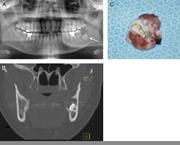

Unicystic ameloblastoma metastasizing to multiple cervical lymph nodes

Kazuma Noguchi and others

Journal of Surgical Case Reports, Volume 2013, Issue 5, May 2013, rjt033, https://doi.org/10.1093/jscr/rjt033